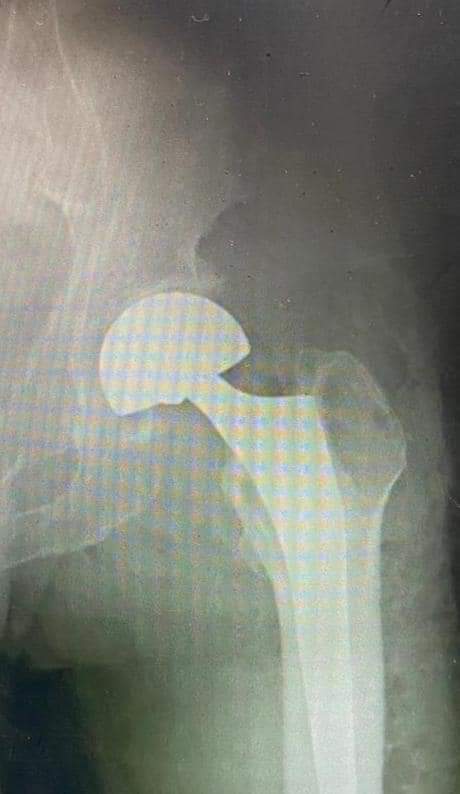

يقوم بعمليات تثبيت الكسور المعقدة بشكل طاريء وتبديل المفاصل بشكل مبرمج مما خفف على المواطنين البحث عن أسرة في مستشفيات مركزية رغم صعوبة عمليات العظام من الناحية التقنية في المستشفيات النائية إضافة الى استقبال اعداد كبيرة بالعيادات ومعالجة جميع المرضى بالطرق المثلى انه الدكتور الانسان البارع والمتميز يزيد البريزات طبيب العظام في مستشفى الاميرة سلمى / ذيبان عيادة العظام علماً بأنه كان مستشفى تحويلي منذ تاسيسه والدكتور البربزات وقبل اربع سنوات في عام 2020 منذ انتقاله للمستشفى يقوم بهذه العمليات ومن بينها عمليات نوعية لمرضى يعانون من كسور معقدة في الترقوة واجراء عمليات دقيقة ومعقدة لكسور لمرضى في مختلف أنحاء الجسم وعمليات تثبيت الكسور المعقدة وتركيب المفاصل وغيرها الكثير والديسك " وآلامه وتبعاته وعلاجه وإجراء عمليات معقده وصعبه.

وأجرى الدكتور البريزات عمليات كبرى في جراحة العظام والتي تحتاج إلى مراكز متقدمة ومتطورة. وكذلك العمل على تثبيت أغلب انواع الكسور بطريقة طارئة وتبديل المفاصل بطريقة مبرمجة بما يتناسب مع امكانات المستشفى والتي هي جزء من العمليات الدورية بمستشفى الاميرة سلمى في ذيبان والتي تخفف العبئ على المستشفيات المركزية وعلى المواطن في آن واحد.

وعبر كثير من المرضى وذويهم عن عظيم شكر هم وامتنانهم للدكتور البريزات على ما بذله ويبذله من جهود كبيرة واستثنائية في تعامله مع المرضى والمراجعين ومتابعته الحثيثة لهم والاطمئنان عليهم والتي تكللت جميعها بالنجاح وله الدور الكبير برفع كفاءة قسم العظام بالمستشفى بشكل عام والذي أصبح متطوراً بالقيام بالعمليات مثل تثبيت الكسور المعقدة و تركيب المفاصل و غيرها.